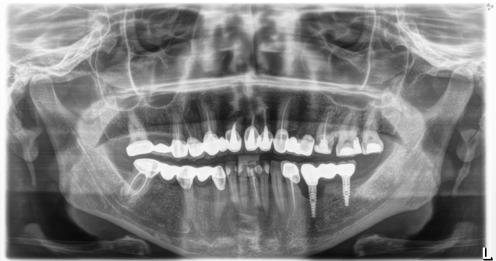

1. ábra: A 12. fog - a röntgenfelvételen nagyméretű periapikális elváltozás látható. A tünetmentes fogat ISO 25/.06 TF Adaptive reszelővel (Kerr Dental) preparáltuk. – 2. ábra: A 12. fog gyökércsatornájának tömését ásványi trioxid aggregátummal (ENDOSEAL MTA, Maruchi) végeztük. Figyeljük meg az apikális elágazás lezárását, ami az apikális terminus hatékony tisztítása és dekontaminálása miatt lehetséges. A gyógyulás 12 hónap elteltével csaknem teljes volt. – 3. ábra: 33. fog - a páciensnél egy bukkális sinus traktus volt látható, amely röntgenfelvételen a 32. és a 33. fog közötti területnek felelt meg. A CBCT és a röntgenfelvétel nagyméretű periradikuláris elváltozást mutatott, különösen a disztális oldalon. A preparálást 20/,07v ProTaper Gold (F1; Dentsply Sirona) készülékkel végeztük. – 4. ábra: A 33. fog gyökércsatorna obturációját sealer és hordozó alapú guttapercha (AH Plus és Thermafil, Dentsply Sirona) segítségével végeztük. A hat hónappal a műtét után végzett röntgenellenőrzés azt mutatta, hogy több oldalsó csatorna feltöltődött, és a gyógyulási folyamat folyamatban van.

keletkeznek [25-29]. A másodlagos kavitációs buborékok összeomlásuk során a csatornafalak közvetlen közelében vannak, nyírófeszültséget és örvényes áramlásokat generálva, amelyek képesek eltávolítani a törmeléket, a kenetréteget és a biofilmet a gyökércsatorna felszínéről, valamint a fel nem fedezett és műszerrel nem rendelkező anatómiai területekről, például az isztmuszokból, az oldalsó csatornákból, a hurkokból és a ramifikációkból, ezáltal tovább fokozva a tisztítási és dekontaminációs mechanizmust (1-4. ábra). A gyökércsatorna mentén létrejövő fokozott nyomás következésképpen az irrigálószereknek a dentinális tubulusokba való behatolásának mélységét is növeli [25-28].